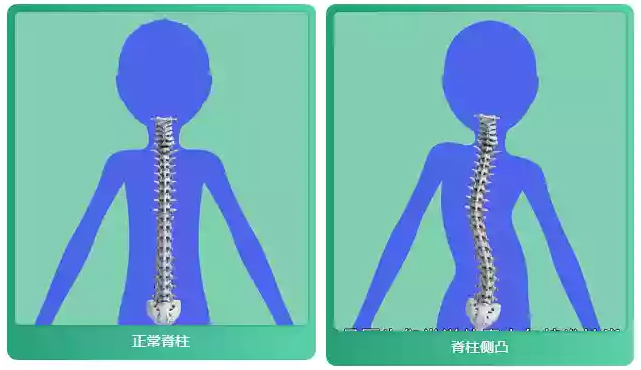

从解剖学角度来看,脊柱的外观特征如下:

- 从前方向后看,脊柱应当呈现为一条直线。

- 从侧面观察,脊柱具有四个主要的生理弯曲:颈椎和腰椎呈现出前凸(即向外突出),而胸椎和骶椎则显示出后凸(即向内凹陷)。

脊柱侧弯是一种脊柱偏离正常中线位置,形成大于10度的C形或S形非正常弯曲的情况。青少年特发性脊柱侧弯(Adolescent Idiopathic Scoliosis, AIS)是最常见的脊柱侧弯类型之一,主要影响年龄在10岁至骨骼成熟期之间的儿童和青少年。AIS的发病率大约在2%到4%之间,而且女孩的发病率显著高于男孩。